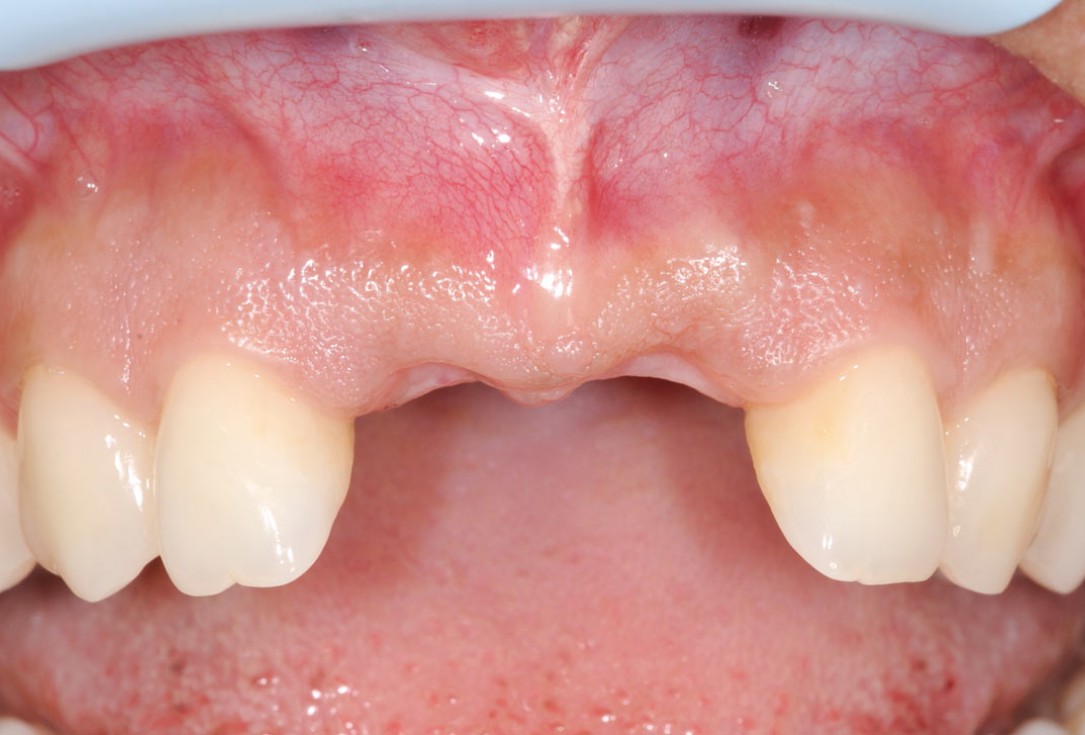

1/26 - Initially bridge retained incisorsBone augmentation in aesthetic zone with maxgraft® bonering - Dr. A. Patel